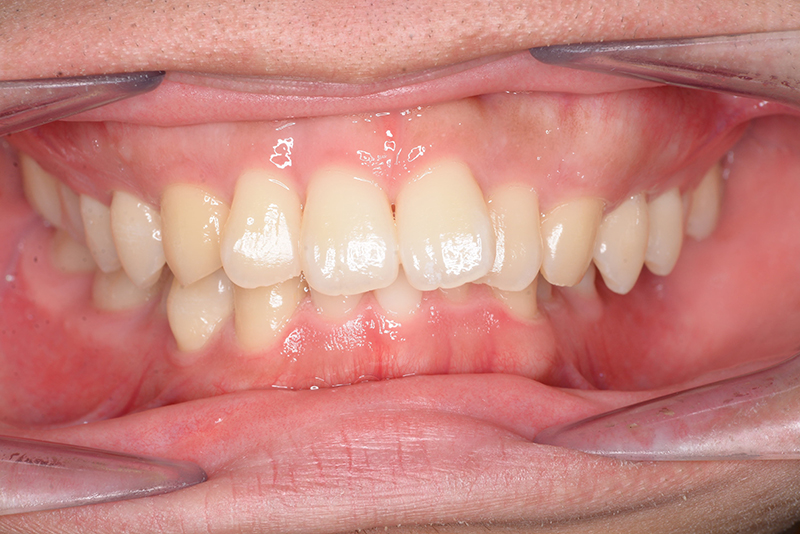

動的治療終了時

FP・IOP

批評・予后 左側臼歯uprightによって鋏状咬合、過蓋咬合の改善が得られた。下顎前歯先欠によるAnterior ratio不調和と上顎前歯部叢生の改善を目的とし、上顎前歯にIPRを行ったが、治療後において左上2付近のover jetが大きく、上顎犬 歯間幅径の拡大(1.5mm)も生じているため、後戻りの懸念が残る。口元や歯列の安定性を考慮し、小臼歯抜歯も検討したがハイアングルであり下顎3-incisalのため、治療が困難となる事を危惧して非抜歯にて治療を行った。